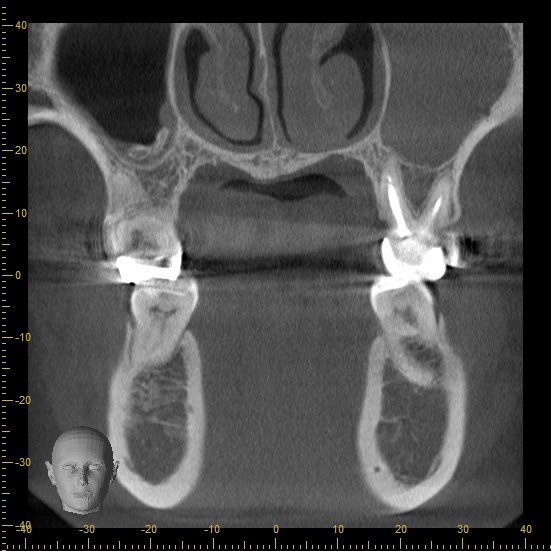

レントゲンを見てみます。

親知らずがあったせいでしょうか。

歯の根元に歯石が付いていて、その周りの骨が吸収しています。

手術直後のレントゲン写真です。

歯石は取れていますが、もちろん骨は溶けたままで凹んでいます。